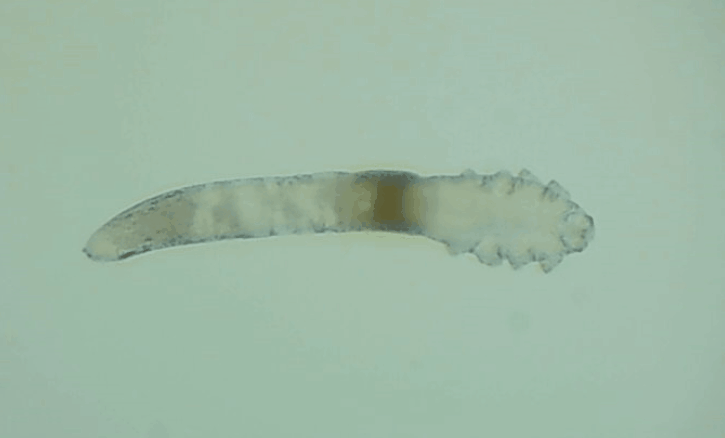

是的, 眼睛也會有蟲子,那就是蠕形螨。眼睛發(fā)紅、干癢、疲勞、睫毛脫落,這些都是因為它。

其實蠕形螨主要活動在毛囊和皮脂腺中,以皮膚碎屑和腺體分泌物作為食物來源,而睫毛根部的瞼板腺是排泄油脂的重要部位,因此眼睫毛和瞼板腺也是螨蟲的主要活動場所。

一般來說,15天內,一只蠕形螨會在你眼睛里產下50只蟲卵。如果不及時除螨,它們會迅速繁殖,從而導致睫毛脫落、亂生、眼睛紅癢,甚至引發(fā)眼部炎癥。如果影響到角膜,就會造成視力下降甚至失明。